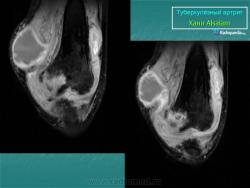

Туберкулез коленного сустава (гонит)

Поражение коленного сустава при туберкулезе встречается часто, на его долю приходится около 20% всех случаев костно-суставного туберкулеза. Общие клинические симптомы в преартритической фазе связаны с интоксикацией. Местные проявления или совсем отсутствуют, или носят неопределенный характер и мало выражены, однако больной заметно щадит пораженную конечность. Преартритическая фаза может протекать длительно, особенно в детском возрасте, в связи с тем, что эпифизы покрыты толстым суставным хрящом. Первичные очаги чаще встречаются в проксимальном эпифизе большеберцовой кости (50%) и в дистальном эпифизе бедренной кости (21,7%), реже в метафизах этих костей (соответственно в 10% и 2,3% случаев), и совсем редко в надколеннике и эпифизе малоберцовой кости (2,2%). Первым рентгенологическим симптомом туберкулезного процесса является ограниченный участок остеопороза с нечетким рисунком костных трабекул. Затем появляется нечетко очерченный очаг деструкции костной ткани, который может содержать губчатые мелкие секвестры. Очаги деструкции могут быть крупными, нередко в форме песочных часов, что характерно именно для поражения коленного сустава. При наиболее частой, эпиметафизарной локализации, очаги деструкции костной ткани обычно располагаются субкортикально. Периоститы не характерны. Артритическая фаза туберкулезного гонита характеризуется постоянством клинических проявлений. Появляется небольшая атрофия мышц, симптом Александрова, припухлость и боли в суставе, контрактуры, повышение местной температуры. Причем эти симптомы сохраняются и в покое. У некоторых детей отмечается удлинение пораженной конечности. Сустав увеличен в объеме, постепенно нарастает атрофия мышц, подвывихи голени, чаще кзади. Появляются натечные абсцессы и свищи. Рентгенологические проявления туберкулезного гонита достаточно разнообразны. Однако самым ранним симптомом перехода туберкулезного процесса на сустав является нарастающий диффузный или пятнистый остеопороз, который постепенно распространяется на кости всей конечности. Причем, чем более остро протекает туберкулезный процесс, тем более выражен остеопороз. У детей отмечается увеличение размеров эпифизов, по сравнению со здоровой конечностью, одновременно может увеличиваться ядро окостенения надколенника (симптом «постарения эпифизов» С. Л. Трегубова). Постепенно нарастает сужение суставной щели, которое иногда может быть неравномерным, больше выраженным с одной стороны. Однако этот признак иногда может быть кажущимся, и связан с небольшой сгибательной контрактурой. В таких случаях необходимо производить для сравнения рентгенографию и здорового коленного сустава в том же положении. Одновременно с сужением суставной щели появляется неровность, волнистость суставных поверхностей, затем появляется нечеткость, зазубренность, прерывистость контуров суставных поверхностей. Выявляются краевые очаги деструкции костной ткани, которые могут располагаться в противоположных отделах сочленяющихся костей и содержать секвестры, часто множественные. Секвестры кажутся более плотными, «склерозированными» на фоне выраженного остеопороза, структура их губчатая, «ноздреватая», контуры неровные. Постепенно появляются признаки истинной атрофии костей. При затихании процесса рентгенологически не отмечается прогрессирование деструкции. Контуры очагов деструкции становятся сначала четкими, а затем вокруг них появляется нежный ободок склероза. Выявляются контуры суставной щели, которая имеет причудливую форму. На уровне очагов деструкции она неравномерно расширена, а в тех отделах, где замыкательные пластинки эпифизов сохранены резко сужена. На фоне остеопороза появляются толстые, склерозированные костные балки, расположенные вдоль силовых линий. Постепенно восстанавливаются и уплотняется замыкательнные пластинки эпифизарных концов сочленяющихся костей. Суставная щель суживается, иногда вовсе не прослеживается. Костные анкилозы наблюдаются не часто, более типичны фиброзные сращения, порочное положение и подвывихи. У детей нарушается продольный рост костей и отмечается их укорочение. В менее благоприятных случаях наблюдаются обострения и рецидивы, что связано с наличием остаточных туберкулезных очагов. В этих случаях нарастают явления интоксикации и местные изменения. При рентгенологическом исследовании выявляется нарастание остеопороза, появляются очаги деструкции с нечеткими, неровными контурами, иногда содержащие секвестры. Замыкательные пластинки также теряют четкость. Деструктивные изменения могут быть значительными и приводить к дальнейшему разрушению костей, образующих сустав. Дифференциальную диагностику туберкулезного гонита приходится проводить с целым рядом заболеваний: частичным асептическим некрозом (болезнь Кенига), литическим вариантом остеобластокластомы, остеогенной остеокластической саркомой, гемофилическим артрозом и ревматоидным артритом. Болезнь Кенига встречается у взрослых. Больных беспокоят боли в коленном суставе, усиливающиеся при нагрузке. Симптомы интоксикации отсутствуют. Дифференцировать с туберкулезным процессом приходится I—II стадии болезни Кенига. Однако отсутствие остеопороза, типичная локализация краевого очага деструкции в медиальном мыщелке бедра, его небольшие размеры, относительно четкие контуры, наличие плотного с четкими контурами секвестроподобного тела, обычные размеры суставной щели — все это позволяет высказаться в пользу частичного асептического некроза. При дифференциальной диагностике с остеогенной остеокластической саркомой, которая особенно в начальных стадиях протекает без постоянных болей, может возникнуть ряд трудностей. Однако у детей остеогенная саркома локализуется в метафизе. Очаг деструкции одиночный с неровными, нечеткими контурами, не содержит секвестров, остеопороз в прилежащих отделах костной ткани не характерен. Типична периостальная реакция по смешанному типу. Раньше существовала точка зрения, что при саркоме процесс не переходит через ростковую зону. В последние годы доказана возможность у детей перехода процесса при остеогенной саркоме через ростковую зону. Однако разрушения суставного хряща и сужения суставной щели не отмечается. При литическом варианте остеобластокластомы очаг деструкции костной ткани, локализуясь в эпиметафизе у взрослых и метадиафизе у детей, чаще располагается эксцентрично, вызывая на ранних стадиях асимметричное булавовидное вздутие кости. Очаг деструкции имеет четкие контуры. Склеротическое отграничение и наличие секвестров не типично. Остеопороза в прилежащих отделах не выявляется. При проведении дифференциальной диагностики с гемофилическим артрозом необходимо учитывать клинические, анамнестические и лабораторные данные. У больных с гемартрозом отсутствуют явления интоксикации, в анамнезе имеется указание на кровоточивость, свертываемость крови замедлена. Кроме того, при гемофилии, как правило, поражаются несколько суставов. При рентгенологическом исследовании может выявляться остеопороз, который захватывает эпифизы и не бывает таким распространенным, как при туберкулезе. Может наблюдаться увеличение размеров эпифизов по сравнению со здоровой стороной. Контуры замыкательных пластинок неровные, но всегда четкие, секвестры отсутствуют. В ряде случаев может возникнуть необходимость в проведении дифференциальной диагностики с ревматоидным артритом,, который в детском возрасте иногда может начинаться с поражения одного сустава. В этих случаях необходимо учитывать длительность заболевания, клинические и лабораторные данные. При ревматоидном артрите характерна скованность движений по утрам, отсутствие симптомов интоксикации, отрицательный симптом Александрова. Туберкулиновые пробы, как правило, отрицательные. Диагностическое значение имеет положительный ревматоидный фактор в синовиальной жидкости. При рентгенологическом исследовании больных ревматоидные артритом выявляется остеопороз костей образующих коленный сустав, сужение суставной щели. У мест прикрепления капсулы сустава выявляются краевые узуры с четкими контурами и ободком склероза вокруг. При туберкулезном гоните — в эпиметафизе большеберцовой и бедренной костей выявляются очаги деструкции с нечеткими, изъеденными контурами, постепенно переходящими в остеопоротичную костную ткань. Очаги деструкции могут содержать губчатые секвестры.